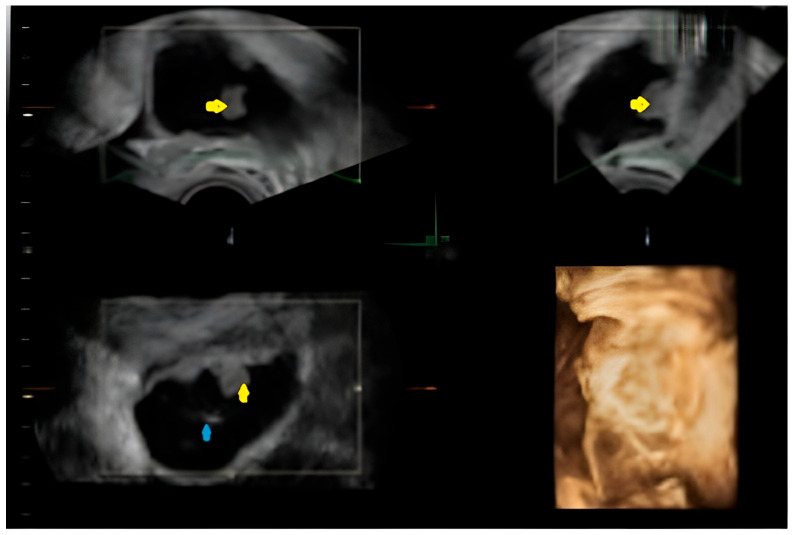

背景:息肉样子宫内膜异位症是一种罕见的子宫内膜异位症,表现为肿瘤肿块,很难与恶性肿瘤区分。它通常发生在围绝经期妇女或接受激素治疗的妇女中,在年轻孕妇中出现极为罕见。病例介绍:这篇文章描述了一个罕见的妊娠妇女的息肉样卵巢子宫内膜异位症,在医学文献中很少有记录的病例。在常规产前超声检查中偶然发现附件肿块,其影像学特征引起了肿瘤过程的怀疑,并提示手术排除恶性肿瘤。然而,切除病变的组织病理学检查证实了与息肉样子宫内膜异位症相符的特征,没有发现癌症的证据。本病例强调了鉴别子宫内膜异位症与卵巢肿瘤的诊断挑战,特别是在妊娠期间,影像学表现可能不明确。此外,妊娠期固有的激素环境可能加剧子宫内膜异位症病变的增殖行为,从而使临床评估复杂化。在这种情况下,附件肿块的存在通常需要仔细评估,以平衡手术风险和延迟诊断的潜在后果。提出的数据强调了准确诊断的重要性。最后,协调良好的做法可确保保护孕产妇和胎儿健康。结论:通过优先准确的诊断和个性化的治疗方案,医生可以最大限度地减少并发症,改善母亲和孩子的预后。

Background: Polypoid endometriosis is a rare variant of endometriosis that presents as a tumorous mass, making it difficult to differentiate it from a malignant tumor. It usually occurs in perimenopausal women or those undergoing hormone therapy, and its presence in a young pregnant woman is extremely uncommon. Case Presentation: This article describes a rare instance of polypoid ovarian endometriosis in a pregnant woman, a condition with few documented cases in the medical literature. An adnexal mass was discovered incidentally during a routine prenatal ultrasound, with imaging features that raised the suspicion of a neoplastic process and prompted surgery to exclude malignancy. However, histopathological examination of the excised lesion confirmed features compatible with polypoid endometriosis, without revealing evidence of cancer. This case highlights the diagnostic challenges of differentiating polypoid endometriosis from ovarian neoplasms, especially during gestation, where imaging findings can be ambiguous. In addition, the hormonal environment inherent in pregnancy may exacerbate the proliferative behavior of endometriotic lesions, thus complicating clinical evaluations. The presence of an adnexal mass in such a setting often requires careful evaluation to balance the risks of surgery with the potential consequences of delayed diagnosis. The data presented emphasize the importance of an accurate diagnosis. In conclusion, a well-coordinated approach ensures the protection of maternal and fetal health. Conclusions: By prioritizing accurate diagnosis and personalized treatment plans, physicians can minimize complications and improve outcomes for both mother and child.